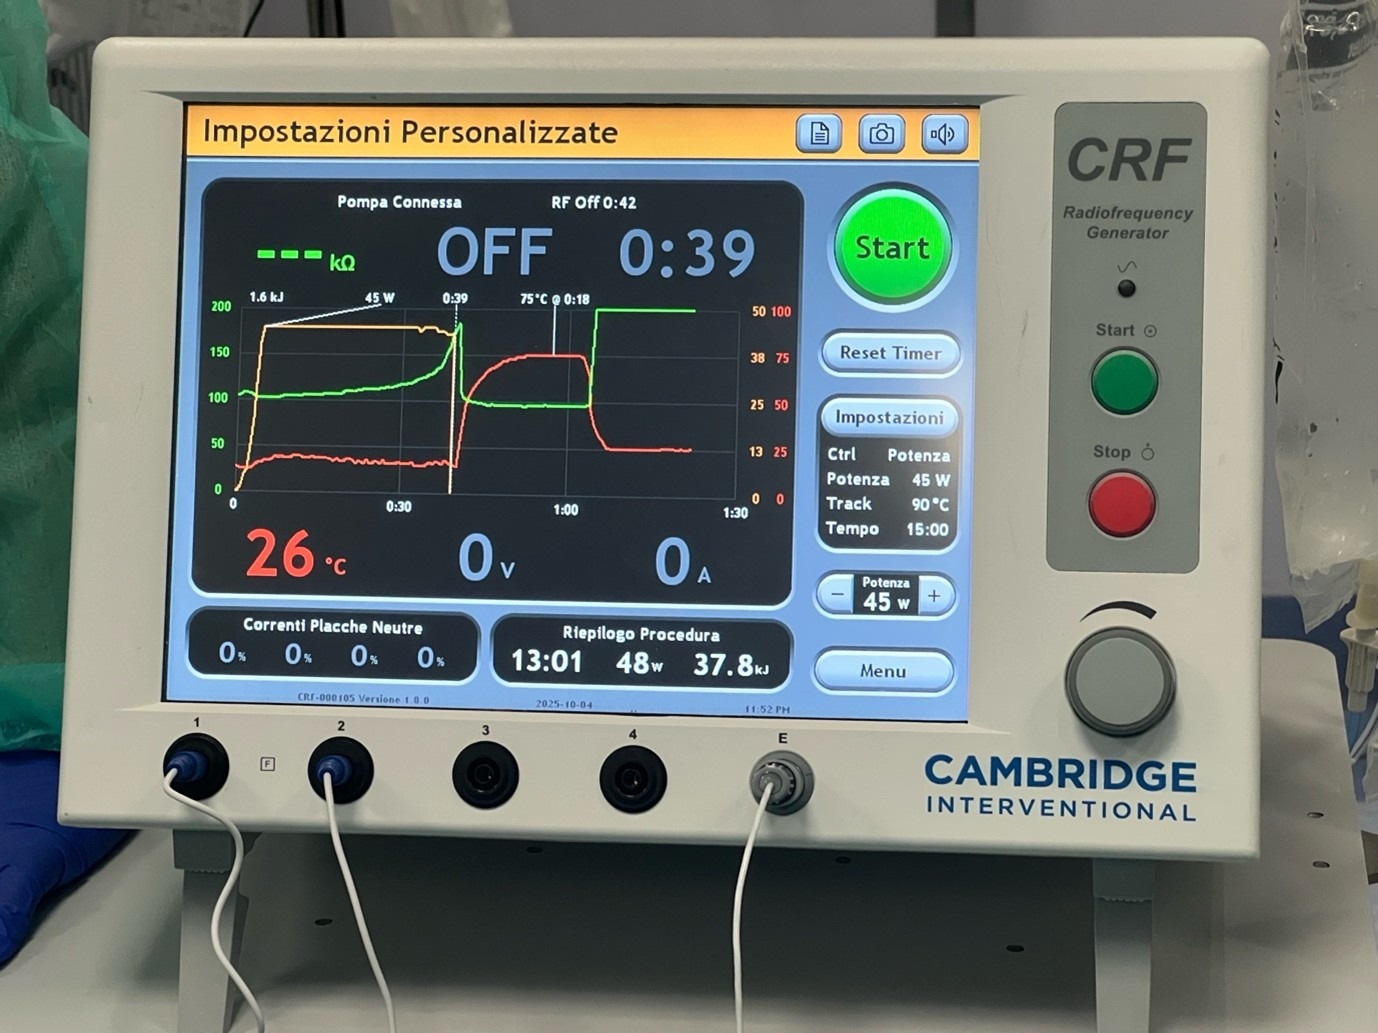

- Thermal ablation with radiofrequency, microwave, and cryoablation

In addition to gaining insight into some of the different modalities available and the pros and cons of various manufacturers and cases, I also was able to observe differences in the imaging equipment used and the room setup, an insight that I will take back with me. Sometimes this would be as simple as the way a patient was prepped and draped right up to the intricacies of complex image fusion equipment and the benefit it could have on a case.

On the topic of equipment, the main theatre suite is a well-equipped and spacious room with good access to anaesthetic support. Many complex cases were made easy by the availability and assistance of the anaesthetists and willingness to employ techniques such as single lung ventilation. The angio-CT equipment meant that all eventualities were catered for and the entire range of procedures could be performed with the patient on one table. Both CT navigation equipment and US/CT fusion equipment were used very routinely to help make challenging cases safer and less time-consuming. In particular, it was interesting to note that these were routinely used even in less challenging cases to ensure that staff were all experienced and familiar with the equipment. This really showed as the setup and implementation took very little additional time. I had never used ultrasound-fusion before but was reassured to see how smoothly it could be implemented into an IR procedure.

Another technology I was fortunate to witness was the use of ablation confirmation software. Up until now, I have experienced basic versions of this, so it was useful to see a modern software package in action and to note the clinical impact it had, whereby two liver lesions were re-ablated to try to ensure optimum coverage and reduce risk of disease recurrence.